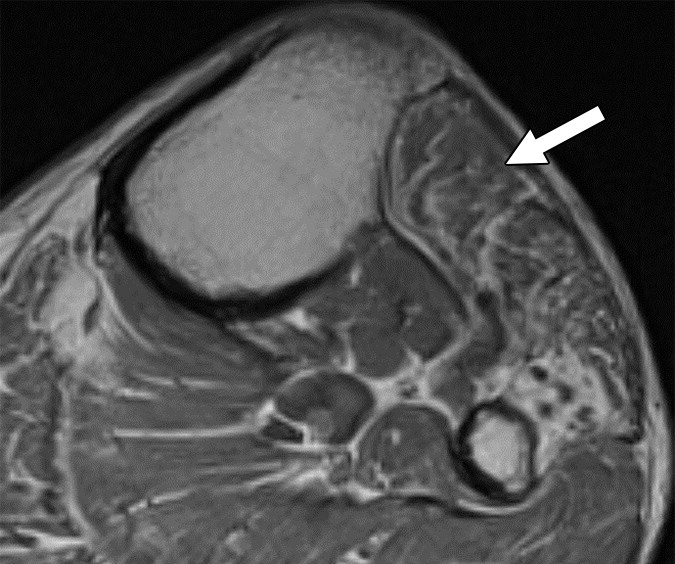

On the basis of the overall promising interrater agreement shown in this study, we believe that the newly proposed NS-RADS classification will perform as well in routine practice as it did in this initial validation study (Fig. 3).